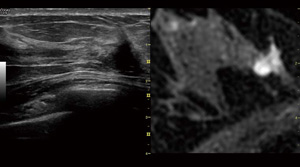

●Volume NavigationでMR画像と対比

超音波の高分解能やリアルタイム性と,MRIの高感度や客観性を組み合わせることが可能です。リアルタイムに超音波とMRIの対比画像が表示されますので,詳細な比較検討が行えます。拡がり診断,副病変の確認,セカンドルック,手術範囲の評価などに期待されます。

Volume Navigation